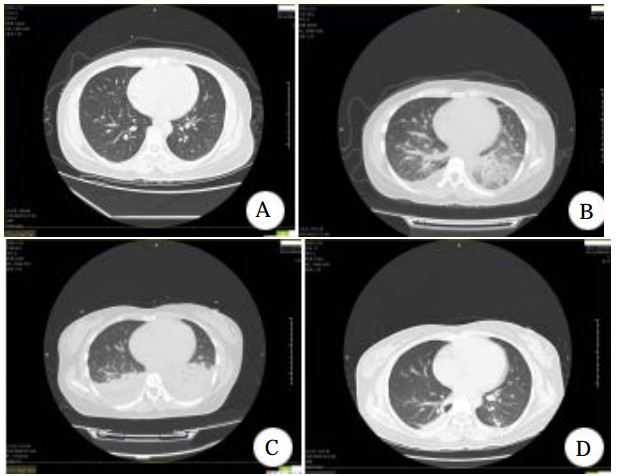

1 资料与方法患者女,33岁,因情绪低落自服硝苯地平片(规格10 mg)七八十片,约半小时后出现呕吐,呕吐物为内容物,15 h后出现胸闷,伴少许咳嗽,无胸痛,无呼吸困难,无咳痰,家属送至当地基层医院就诊,急诊测血压92/48 mmHg(1 mmHg=0.133 kPa),予补液升压等治疗后转入本院,查体一般情况良好,意识清楚,体温38℃,呼吸26次/min,血压87/61 mmHg,心率110次/min,心律齐,未闻及病理性杂音,两肺呼吸音清,未闻及啰音,口唇无发绀,颈静脉无怒张,腹平软,肝脾无肿大,双下肢无水肿。实验室检查:超敏C反应蛋白 < 0.50 mg/L,白细胞数10.49×109/L,中性粒细胞百分数88.7%,血红蛋白109.0 g/L;肌酐106 μmol/L,血气分析、凝血功能、D-二聚体、肌钙蛋白、肝功能等均无明显异常。胸部CT示两肺下叶少许慢性炎症性改变(图 1A)。

| 图 1 患者胸部CT(A:入院前;B:入院第1天;C:入院第4天;D:入院第7天) |

患者入院后,予心电监护,测血压并积极补液、导泻、利尿等对症治疗,但患者拒绝血液灌流治疗。入院10余个小时后,患者出现了胸闷咳嗽,氧饱和度下降至90%,予鼻导管吸氧后经皮氧分压维持在95%左右,入院1 d后氧饱和度降至88.4%,查肌钙蛋白0.136 ng/mL,B型脑钠肽为575.9 pg/mL,均为轻度升高。复查胸部CT出现两肺肺水肿和双侧少量积液(图 1B),查腹部CT亦发现胆囊窝区、胰周渗出改变,腹腔积液(图 2A)。血压进一步降至58/42 mmHg,予多巴胺10μg/(kg·min)收缩血管升压,持续输注葡萄糖酸钙(10 mL/12 h)对抗硝苯地平的钙拮抗剂作用,人血白蛋白(10 g/12 h)补充胶体渗透压,葡萄糖生理盐水(500 mL qd)补液,甲泼尼龙(40 mg/d)抗炎,还原型谷胱甘肽(2.4 g/d)护肝,托拉塞米(20 mg/d)利尿等治疗处理。多巴胺升压使用2 d后转用去甲肾上腺素(8 mg为泵注射)继续使用2 d,药物维持下血压可达(102~122)/(52~68)mmHg。入院4 d,撤去升血压药物后,收缩压能够维持在90 mmHg以上并动态监护未再出现低血压。入院第四天复查胸部CT提示两侧胸腔积液增多(图 1C),腹部CT提示胰周渗出减少(图 2B),继续当前治疗。入院第七天胸腔积液、肺水肿以及腹腔积液几乎完全吸收(图 1D、图 2C)。经过12 d的治疗后患者胸闷气促、咳嗽咳痰完全好转。出院一个月后随访患者未再服用硝苯地平,也未出现上述不良症状。